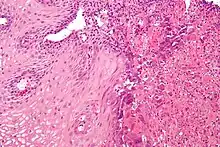

Although it usually assumed that inflammation from acid reflux is caused by the irritant action on the mucosa by hydrochloric acid, one study suggests that the pathogenesis of reflux esophagitis may be cytokine-mediated.[6]